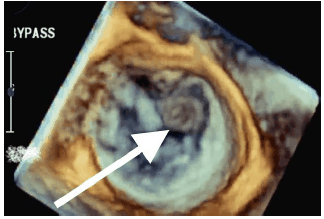

Homem de 65 anos, internado devido ataque isquêmico transitórico, submetido a ecocardiograma transesofágico 3D para pesquisa de fonte emboligênica diagnosticando fibroelastoma papilar (seta).

Identifique em que scallop está localizada a patologia demonstrada pela seta.